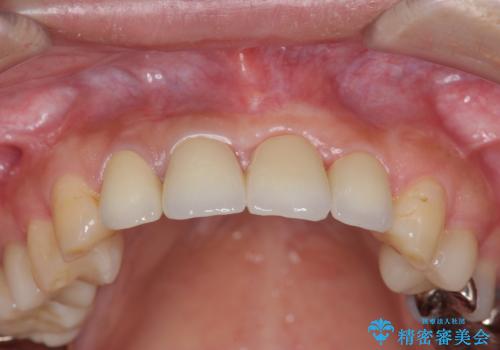

不良インプラントを除去し最終的にブリッジによる補綴で審美性の改善を行うこと、その準備として骨の造成・歯肉の移植による歯の欠損部顎堤のボリュームを維持・増大を計画します。

より審美的な改善を強く求められたため、インプラントを除去し可及的に欠損部顎堤を増大したのちブリッジによる審美改善を行いました。